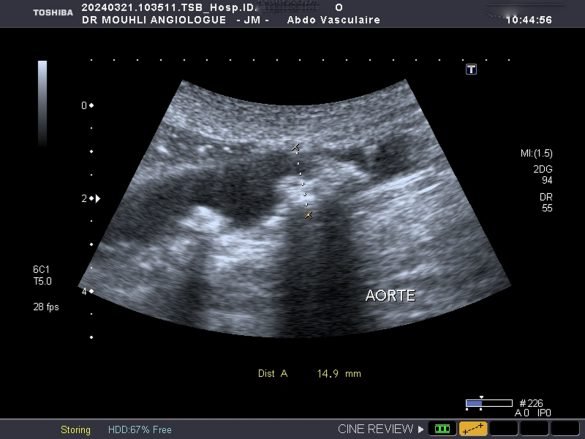

Appareil circulatoire pathologieArtère pathologieAthéroscléroseCentre d’apprentissageChirurgieechodopplerTraitementVaisseau sanguin pathologie L’aorte : La plus grande artère du corps et les dangers de l’athérosclérose by jamel MOUHLI 11 juillet 2024 written by jamel MOUHLI 11 juillet 2024 0 comments 22 minutes read Bookmark 496 L’aorte est la plus grosse artère du corps. Partant du cœur, elle achemine le sang vers les jambes en passant par le thorax et l’abdomen. Elle décrit d’abord un trajet ascendant puis effectue un virage (crosse) où naissent les artères à destination des bras et du cerveau. Elle descend ensuite dans le thorax en vascularisant la moelle épinière. Une fois au niveau du diaphragme, elle devient l’aorte abdominale où le sang est distribué dans les artères du tube digestif (tronc cœliaque donnant les artères hépatique et splénique, artère mésentérique supérieure, artère mésentérique inférieure) et des reins. Les thromboses aortiques sont le plus souvent liées à la présence de lésions athéromateuses au sein de la paroi aortique chez des patients avec des facteurs de risques cardio-vasculaires. De rares cas surviennent sur artère saine et sont alors considérés comme « isolés ». L’athérosclérose est responsable de nombreuses maladies cardio-vasculaires qui représentent la première cause de mortalité dans le monde. QU’EST-CE QUE L’ATHÉROSCLÉROSE ? L’Athérosclérose ou artériosclérose correspond à un dépôt de graisses formant une plaque d’athérome qui rétrécit le passage du sang. QUELLES SONT LES CONSÉQUENCES DE L’ATHÉROSCLÉROSE ? Les conséquences de la plaque d’athérome sont multiples dont la rupture à l’origine d’accident vasculaire grave. L’athérosclérose peut toucher différents organes. Un rétrécissement d’aorte Un rétrécissement des artères carotides peut entraîner un accident vasculaire cérébral. En cas d’atteinte des artères des jambes, on parlera d’artériopathie oblitérante ou artérite des membres inférieurs. L’atteinte des artères coronaires peut entraîner des infarctus du myocarde. Le mode de révélation clinique de la thrombose Claudication fessiére ;pieds froids et absence de pouls périphérique Il s’agit du cas typique d’une patiente présentant une sténose de l’aorte abdominale sous-rénale (sténose de l’aorte basse) à extension iliaque, découverte à l’occasion de la persistance de douleurs dorsales à irradiation fessière. une ischémie aiguë de membre dans 8 cas sur 10. écho-Doppler artériel THROMBOSE AORTE SOUS RENALE SUR ANEVRISME THROMBOSEE AORTE NORMALE un scanner thoraco-abdominal injecté, Les cas survenant sur artère saine sont difficiles à dénombrer et le terme de thrombus « isolé » est peut-être employé par défaut. L’hypothèse d’une lésion athéromateuse focale isolée induisant un thrombus, ou des pathologies inflammatoires diagnostiquées sur l’examen anatomopathologique du thrombus l’illustrent. POURQUOI UN ÉCHODOPPLER ? Introduction à l’aorte L’aorte, la plus grande artère du corps humain, joue un rôle crucial dans la circulation sanguine. Elle naît du ventricule gauche du cœur et constitue le principal conduit par lequel le sang oxygéné est distribué à l’ensemble du corps. L’anatomie de l’aorte est complexe et se divise en plusieurs segments : l’aorte ascendante, l’arc aortique, l’aorte thoracique descendante et l’aorte abdominale. Chaque segment est responsable de l’acheminement du sang vers différentes parties du corps, assurant ainsi un approvisionnement constant en oxygène et en nutriments essentiels. L’aorte ascendante commence au niveau du cœur et monte vers le haut, tandis que l’arc aortique courbe vers l’arrière et la gauche, donnant naissance à plusieurs grandes artères qui irriguent la tête, le cou et les membres supérieurs. L’aorte thoracique descendante poursuit son trajet à travers le thorax, alimentant les organes vitaux comme les poumons et les parois thoraciques. Enfin, l’aorte abdominale traverse le diaphragme et descend jusqu’au bas de l’abdomen, où elle se divise en artères iliaques, fournissant du sang aux organes abdominaux, pelviens ainsi qu’aux membres inférieurs. La fonction principale de l’aorte est de maintenir une circulation sanguine continue et efficace, essentielle pour le bon fonctionnement des organes et des tissus corporels. Grâce à ses parois épaisses et élastiques, l’aorte supporte la pression élevée générée par chaque contraction cardiaque, facilitant ainsi la propulsion du sang à travers le réseau artériel. La structure robuste de l’aorte permet non seulement de résister aux variations de pression sanguine, mais aussi de réguler le flux sanguin, garantissant une distribution homogène et adéquate du sang dans tout le corps. Trajet et divisions de l’aorte L’aorte, la plus grande artère du corps humain, joue un rôle crucial dans la circulation sanguine en transportant le sang oxygéné du cœur vers les différentes parties du corps. Elle commence son parcours depuis le ventricule gauche du cœur sous la forme de l’aorte ascendante. Cette section initiale de l’aorte s’élève pour atteindre la base du cou, où elle forme un arc connu sous le nom de crosse aortique. La crosse aortique est une structure clé car elle donne naissance à plusieurs artères importantes qui irriguent des régions vitales du corps. Parmi celles-ci, nous trouvons les artères carotides qui alimentent le cerveau, ainsi que les artères subclavières qui fournissent le sang aux bras. Ces ramifications sont essentielles pour assurer un apport constant et adéquat en oxygène et nutriments à ces parties critiques du corps. Après la crosse aortique, l’aorte poursuit son chemin en devenant l’aorte descendante, qui se divise en deux parties : l’aorte thoracique et l’aorte abdominale. L’aorte thoracique traverse la cavité thoracique, fournissant des branches qui irriguent la moelle épinière, les parois thoraciques et les structures pulmonaires. Lorsque l’aorte atteint le diaphragme, elle devient l’aorte abdominale. Cette partie de l’aorte est responsable de la distribution du sang aux organes abdominaux par l’intermédiaire de diverses branches artérielles. Parmi ces branches figurent les artères rénales, qui alimentent les reins, et les artères mésentériques, qui irriguent le tube digestif. La division terminale de l’aorte abdominale forme les artères iliaques communes, qui fournissent le sang aux membres inférieurs. L’intégrité structurelle et fonctionnelle de ces divisions de l’aorte est essentielle pour maintenir une circulation sanguine efficace dans tout le corps. Toute perturbation, telle que l’athérosclérose, peut entraîner des complications graves et nécessiter une attention médicale immédiate. L’athérosclérose : Définition et causes L’athérosclérose est une maladie chronique qui se manifeste par l’accumulation de dépôts lipidiques, appelés plaques d’athérome, sur les parois internes des artères. Ces dépôts sont principalement constitués de graisses, de cholestérol, de calcium et d’autres substances présentes dans le sang. Au fil du temps, l’accumulation de ces plaques entraîne un rétrécissement et un durcissement des artères, réduisant ainsi le flux sanguin vers les organes vitaux. Les causes de l’athérosclérose sont multiples et souvent interconnectées. Parmi les principales, on trouve une alimentation riche en graisses saturées et en cholestérol, qui favorise l’augmentation du taux de LDL (Low-Density Lipoprotein) dans le sang. Le LDL, communément appelé « mauvais cholestérol », est l’un des principaux contributeurs à la formation des plaques d’athérome. En revanche, un faible taux de HDL (High-Density Lipoprotein), ou « bon cholestérol », peut également augmenter le risque d’athérosclérose car le HDL aide à éliminer le cholestérol des artères. Le tabagisme est un autre facteur de risque majeur. Les substances chimiques présentes dans la fumée de cigarette endommagent les parois artérielles, facilitant ainsi l’accumulation des dépôts graisseux. De plus, le tabagisme réduit le taux de HDL et augmente la coagulation sanguine, exacerbant le risque de formation de plaques. L’hypertension artérielle, ou pression artérielle élevée, joue également un rôle crucial dans le développement de l’athérosclérose. Une pression excessive contre les parois artérielles peut provoquer des microdéchirures, où les dépôts de graisses peuvent ensuite s’accumuler. De même, le diabète, particulièrement le diabète de type 2, accroît le risque d’athérosclérose en augmentant les niveaux de glucose et de lipides dans le sang. Enfin, des facteurs non modifiables tels que l’âge, le sexe et les antécédents familiaux de maladies cardiovasculaires peuvent également prédisposer un individu à cette pathologie. À mesure que l’on vieillit, les artères ont tendance à devenir moins élastiques, augmentant ainsi le risque d’accumulation de plaques. Les hommes, en particulier, sont plus susceptibles de développer l’athérosclérose à un âge plus précoce que les femmes, bien que le risque pour les femmes augmente après la ménopause. Conséquences de l’athérosclérose L’athérosclérose est une condition grave caractérisée par l’accumulation de plaques d’athérome sur les parois internes des artères, y compris l’aorte, la plus grande artère du corps. Ces plaques peuvent rétrécir ou bloquer les artères, limitant ainsi le flux sanguin vers les organes vitaux. Une des conséquences les plus graves de l’athérosclérose est la rupture de ces plaques, ce qui peut entraîner des accidents vasculaires majeurs et potentiellement mortels. Lorsqu’une plaque d’athérome se rompt, elle peut provoquer la formation de caillots sanguins. Ces caillots peuvent obstruer complètement une artère, entraînant diverses complications selon la localisation de l’obstruction. Par exemple, si une artère coronarienne est bloquée, cela peut causer un infarctus du myocarde, communément appelé crise cardiaque. L’infarctus du myocarde se manifeste par une douleur thoracique intense, un essoufflement et peut mener à une insuffisance cardiaque ou à la mort si non traité rapidement. En outre, si les plaques d’athérome bloquent une artère cérébrale, cela peut entraîner un accident vasculaire cérébral (AVC). Les symptômes d’un AVC comprennent une faiblesse soudaine d’un côté du corps, des troubles de la parole, et une confusion mentale. Un AVC peut entraîner des dommages cérébraux permanents, des incapacités graves, voire la mort. Les soins médicaux d’urgence sont essentiels pour minimiser les dommages lors d’un AVC. L’athérosclérose peut également affecter les artères des membres inférieurs, conduisant à une condition connue sous le nom d’artérite des membres inférieurs. Cette affection se manifeste par des douleurs dans les jambes, particulièrement lors de la marche ou de l’exercice, et peut progresser vers une douleur au repos. Dans les cas graves, l’artérite des membres inférieurs peut provoquer des ulcères ou des gangrènes, nécessitant parfois une amputation. Il est donc crucial de comprendre les conséquences potentielles de l’athérosclérose pour prendre des mesures préventives et consulter un professionnel de la santé pour un diagnostic et un traitement appropriés. Une gestion efficace de cette condition peut aider à prévenir les complications graves et à améliorer la qualité de vie des personnes affectées. Thromboses aortiques : Causes et incidences Les thromboses aortiques représentent un problème grave de santé, souvent associé à des lésions athéromateuses. L’athérosclérose, caractérisée par l’accumulation de plaques de lipides, de cholestérol et d’autres substances dans les parois artérielles, est une cause majeure de ces thromboses. Les patients présentant des facteurs de risque cardiovasculaires tels que l’hypertension, le diabète, et l’hypercholestérolémie sont particulièrement vulnérables à ces lésions. Ces facteurs contribuent à endommager l’endothélium, la couche interne des artères, favorisant ainsi la formation de caillots sanguins. Les thromboses aortiques peuvent aussi survenir, bien que plus rarement, chez des individus sans athérosclérose préexistante. Dans ces cas, des facteurs comme les traumatismes, les infections ou les maladies inflammatoires peuvent jouer un rôle. Par exemple, une dissection aortique, où la paroi de l’aorte se déchire, peut entraîner une thrombose. De plus, certaines conditions génétiques et maladies auto-immunes peuvent aussi prédisposer à la formation de caillots dans une aorte par ailleurs saine. L’incidence des thromboses aortiques varie en fonction de la population étudiée et des facteurs de risque présents. Chez les personnes âgées et celles avec des antécédents de maladies cardiovasculaires, cette incidence est plus élevée. Clinically, les manifestations de la thrombose aortique peuvent être variées. La claudication, qui se traduit par des douleurs musculaires lors de la marche, est un symptôme courant. Les pieds froids, dus à une circulation sanguine réduite, sont aussi fréquents chez les patients atteints. Il est crucial de reconnaître ces signes cliniques pour un diagnostic précoce et une gestion efficace. Les thromboses aortiques non traitées peuvent entraîner des complications sévères, telles que les accidents vasculaires cérébraux et les infarctus du myocarde. Par conséquent, une vigilance accrue et une gestion rigoureuse des facteurs de risque cardiovasculaires sont essentielles pour prévenir ces conditions potentiellement mortelles. Diagnostic des thromboses aortiques Le diagnostic des thromboses aortiques présente une complexité notable, nécessitant une approche méthodique et l’utilisation de technologies d’imagerie avancées. Les thromboses aortiques, qui consistent en la formation de caillots sanguins dans l’aorte, peuvent entraîner des complications graves si elles ne sont pas identifiées et traitées rapidement. Les techniques diagnostiques les plus couramment employées incluent l’écho-doppler artériel et le scanner thoraco-abdominal injecté, chacune offrant des avantages uniques pour la détection des anomalies vasculaires. L’écho-doppler artériel est souvent la première étape dans l’évaluation des thromboses aortiques. Cette technique utilise des ultrasons pour visualiser le flux sanguin et détecter toute obstruction ou anomalie dans l’aorte. L’écho-doppler permet non seulement de confirmer la présence d’une thrombose mais aussi d’évaluer sa taille et son emplacement précis. Toutefois, cette méthode peut être limitée par la qualité de l’image obtenue, surtout chez les patients ayant une anatomie complexe ou de l’athérosclérose avancée. En complément, le scanner thoraco-abdominal injecté, également appelé angioscanner, est une technique d’imagerie par tomodensitométrie (CT) qui fournit des images détaillées de l’aorte et de ses branches. En injectant un produit de contraste intraveineux, l’angioscanner permet de visualiser avec précision les structures vasculaires et d’identifier les thromboses aortiques de manière plus fiable. Cette procédure est particulièrement utile pour évaluer l’étendue des thromboses et planifier une intervention chirurgicale si nécessaire. Cependant, l’exposition aux radiations et les réactions possibles au produit de contraste sont des facteurs à considérer. Le diagnostic des thromboses aortiques demeure un défi en raison des symptômes souvent non spécifiques et de la variabilité dans les présentations cliniques. Une collaboration interdisciplinaire entre cardiologues, radiologues et chirurgiens vasculaires est essentielle pour une évaluation précise et une prise en charge optimale des patients. Les avancées technologiques continues dans les techniques d’imagerie promettent d’améliorer davantage la détection et le traitement des thromboses aortiques à l’avenir. Traitement et prise en charge Une fois la thrombose aortique diagnostiquée, une prise en charge adéquate est cruciale pour prévenir les complications graves. Les options de traitement varient en fonction de la gravité de la condition et peuvent inclure des interventions médicales et chirurgicales. Le traitement médical repose principalement sur la gestion des facteurs de risque athéromateux, tels que l’hypertension, le diabète, l’hypercholestérolémie et le tabagisme. La prise en charge initiale inclut généralement des anticoagulants et des agents antiplaquettaires pour prévenir la formation de nouveaux caillots sanguins. Les statines sont souvent prescrites pour réduire les niveaux de cholestérol et ralentir la progression de l’athérosclérose. Les médecins peuvent également recommander des modifications du mode de vie, telles que l’adoption d’une alimentation saine, l’exercice régulier et la cessation du tabagisme. Dans les cas plus sévères, où l’obstruction de l’aorte est significative ou lorsque des complications telles qu’un anévrisme sont présentes, une intervention chirurgicale peut être nécessaire. Les options chirurgicales comprennent la thrombectomie, qui consiste à retirer le caillot sanguin, et la mise en place de stents pour maintenir l’artère ouverte. Dans certains cas, une chirurgie de pontage aortique peut être réalisée pour contourner les sections obstruées de l’artère. La surveillance continue est essentielle pour les patients ayant des antécédents de thrombose aortique. Un suivi régulier permet d’évaluer l’efficacité du traitement et de détecter toute récidive ou nouvelle complication. Les examens d’imagerie, tels que les échographies et les tomodensitogrammes, sont souvent utilisés pour surveiller l’état de l’aorte. En somme, la gestion des thromboses aortiques est un processus complexe qui nécessite une approche multidisciplinaire. La collaboration entre cardiologues, chirurgiens vasculaires et autres professionnels de la santé est essentielle pour assurer un traitement optimal et améliorer les perspectives à long terme des patients. Prévention de l’athérosclérose et des thromboses aortiques La prévention de l’athérosclérose et des thromboses aortiques est essentielle pour maintenir une bonne santé cardiovasculaire. Cette prévention repose sur une gestion rigoureuse des facteurs de risque cardiovasculaires et sur l’adoption d’un mode de vie sain. Parmi les principaux facteurs de risque à surveiller, on trouve l’hypertension artérielle, le diabète, l’hypercholestérolémie, et le tabagisme. La gestion de ces facteurs est cruciale pour éviter l’accumulation de plaques d’athérome dans l’aorte et les complications qui en résultent. Un mode de vie sain est une pierre angulaire de la prévention de l’athérosclérose. Adopter une alimentation équilibrée, riche en fruits, légumes, fibres et acides gras oméga-3, contribue à maintenir des artères en bonne santé. La réduction de la consommation de graisses saturées et de sucres est également recommandée pour éviter le surpoids et l’obésité, qui sont des facteurs de risque majeurs. L’activité physique régulière, telle que la marche, la natation ou le vélo, aide non seulement à contrôler le poids, mais aussi à améliorer la circulation sanguine et à renforcer le muscle cardiaque. En plus des changements de mode de vie, certains médicaments peuvent être nécessaires pour prévenir l’athérosclérose. Les statines, par exemple, sont fréquemment prescrites pour réduire le taux de cholestérol. Les antihypertenseurs et les antidiabétiques sont utilisés pour gérer l’hypertension et le diabète respectivement. Dans certains cas, les médecins peuvent recommander des anticoagulants pour prévenir la formation de caillots sanguins dans l’aorte, réduisant ainsi le risque de thrombose aortique. L’importance des contrôles médicaux réguliers ne peut être sous-estimée. Des examens de routine permettent de surveiller les niveaux de cholestérol, la pression artérielle, et le taux de glycémie. Ces contrôles aident à détecter précocement tout signe de trouble cardiovasculaire et à ajuster les traitements en conséquence. Les consultations régulières avec un cardiologue ou un médecin généraliste sont donc essentielles pour une gestion proactive de la santé cardiovasculaire. L'Angiologue prend en charge le diagnostic et le traitement de l’ensemble des pathologies des vaisseaux sanguins (artères, veines, lymphatiques) .L'anévrisme aortique est une maladie de l'aorte consistant en une dilatation de cette dernière. Elle peut concerner n'importe quel segment de ce vaisseau. La forme la plus fréquente est l'anévrisme de l'aorte abdominale en dessous des artères rénalesL'anévrisme aortique est une maladie de l'aorte consistant en une dilatation de cette dernière. Elle peut concerner n'importe quel segment de ce vaisseau. La forme la plus fréquente est l'anévrisme de l'aorte abdominale en dessous des artères rénales ARTICLES Bookmark AnatomieAppareil circulatoire pathologieArtère pathologieAthéroscléroseblogsCentre d’apprentissageChirurgieComplicationechodopplerImagerie médicaleL'artère fémoraleTechniqueVaisseau sanguin pathologieVoie endovasculaireVoie percutanée L’athérectomie orbitale : un nouvel outil disponible ,la fin de l\’endarteriectomie ilio-fémorale? by jamel MOUHLI 14 décembre 2025 0 comments 38 views 13 minutes read Post Views: 10 by jamel MOUHLI 14 décembre 2025 Bookmark Voie endovasculaire AORTIC VALVE REPAIR SUMMIT by mouhli 24 octobre 2025 0 comments 522 views 5 minutes read Heading Title L’étude a montré que les personnes atteintes de sténose aortique qui ont subi une intervention chirurgicale pour remplacer une valve rétrécie n’ont qu’une … by mouhli 24 octobre 2025 Bookmark Appareil circulatoire pathologieArtère pathologieAthéroscléroseblogsCentre d’apprentissageI.U.EImagerie médicaleScanner angioScanner Le coroscanner, également connu sous le nom de tomodensitométrie coronarienne, représente une avancée majeure dans le domaine de l’imagerie médicale. by jamel MOUHLI 19 octobre 2025 0 comments 68 views 28 minutes read Introduction au coroscanner Le coroscanner, également connu sous le nom de tomodensitométrie coronarienne, représente une avancée majeure dans le domaine de l’imagerie médicale. Cette technique … by jamel MOUHLI 19 octobre 2025 Bookmark Appareil circulatoire pathologieArtère pathologieAthéroscléroseCentre d’apprentissageComplicationIRM-angioIRMUncategorized Les anévrismes by jamel MOUHLI 15 octobre 2024 0 comments 324 views 11 minutes read Qu’est-ce qu’un anévrisme ? C’est une dilatation anormale d’une artère due à une faiblesse de la paroi du vaisseau sanguin. Cette faiblesse peut entraîner la … by jamel MOUHLI 15 octobre 2024 Bookmark Appareil circulatoire pathologieArtère pathologieAthéroscléroseCentre d’apprentissageChirurgieechodopplerTraitementVaisseau sanguin pathologie L’aorte : La plus grande artère du corps et les dangers de l’athérosclérose by jamel MOUHLI 11 juillet 2024 0 comments 496 views 22 minutes read L’aorte est la plus grosse artère du corps. Partant du cœur, elle achemine le sang vers les jambes en passant par le thorax et l’abdomen. … by jamel MOUHLI 11 juillet 2024 Bookmark Centre d’apprentissage L’ischémie mésentérique by jamel MOUHLI 31 janvier 2024 0 comments 838 views 19 minutes read Importance du bilan vasculaire avant chirurgie hépato-pancréatique Click Here CENTRE APPRENTISSAGE Bookmark Diabete by jamesv10 18 juin 2010 0 comment 8 views {mp4-flv}diabete{/mp4-flv} Association entre … by jamel MOUHLI 31 janvier 2024 Bookmark Appareil circulatoire pathologie la colchicine, le premier médicament anti-inflammatoire pour le traitement des maladies cardiovasculaires by mouhli 17 juillet 2023 0 comments 908 views 9 minutes read La FDA approuve la colchicine, le premier médicament anti-inflammatoire pour … by mouhli 17 juillet 2023 Bookmark Rétrospective Interventions physiques pour interrompre ou réduire la propagation des virus respiratoires by mouhli 23 février 2023 0 comments 614 views 10 minutes read Interventions physiques pour interrompre ou réduire la propagation des virus respiratoires Thomas Jefferson Liz Doley Eliana Ferroni Lubna A Al-Ansary Mieke L van Driel Ghada … by mouhli 23 février 2023 Bookmark Résultat Association de la vaccination par ARNm avec les caractéristiques cliniques et virologiques du COVID- by mouhli 28 octobre 2022 0 comments 1,1K views 9 minutes read Une nouvelle étude publiée sur le Journal of the American Medical Association @JAMANetwork confirme que les personnes non vaccinées ont MOINS de … by mouhli 28 octobre 2022 Bookmark Appareil circulatoire pathologieArtère pathologieAthéroscléroseblogscas cliniquesCentre d’apprentissageChirurgieComplicationechodopplerFeaturedImagerie médicale et droit de la santéNon classéPonctionTechniqueTraitementVaisseau sanguin pathologieVaricesVoie endovasculaireVoie percutanée Les médecins vasculaires (angiologues), les chirurgiens vasculaires et cardiovasculaires, les neurologues, les radiologues interventionnels, les cardiologues interventionnels, les néphrologues, les endocrinologues, les hématologues prennent en charge le diagnostic et le traitement de l’ensemble des pathologies des vaisseaux sanguins (artères, veines, lymphatiques). Les patients sont orientés par leurs médecins généralistes. by mouhli 3 octobre 2022 0 comments 781 views 24 minutes read IUE vise à soutenir l’apprentissage tout au long de la vie des professionnels du secteur cardiovasculaire et endovasculaire. En fournissant une plate-forme de contenu évalué … by mouhli 3 octobre 2022 Bookmark Complication Editorials Thromboembolism and bleeding after covid-19 by mouhli 10 avril 2022 0 comments 481 views 7 minutes read la thrombose veineuse profonde, l’embolie pulmonaire et l’hémorragie L’infection est-elle plus à risque que la vaccination ? Ces risques de thrombose sont également connus … by mouhli 10 avril 2022 Bookmark I.U.E Elon Musk and brother under investigation for alleged insider trading by jamel MOUHLI 24 février 2022 0 comments 637 views 0 minutes read Light pollution is a modern scourge but a concerted effort to bring the darkness to Wales is under way – with the help of astronomy … by jamel MOUHLI 24 février 2022 Bookmark I.U.E Western powers have realised Russia is largely immune to sanctions by jamel MOUHLI 24 février 2022 0 comments 564 views 0 minutes read Light pollution is a modern scourge but a concerted effort to bring the darkness to Wales is under way – with the help of astronomy … by jamel MOUHLI 24 février 2022 Bookmark I.U.E UN resolution deploring invasion vetoed – as it happened right now by jamel MOUHLI 24 février 2022 0 comments 523 views 0 minutes read Light pollution is a modern scourge but a concerted effort to bring the darkness to Wales is under way – with the help of astronomy … by jamel MOUHLI 24 février 2022 Bookmark I.U.E Lockdown lifestyles: how has Covid changed lives around the world by jamel MOUHLI 24 février 2022 0 comments 521 views 0 minutes read Light pollution is a modern scourge but a concerted effort to bring the darkness to Wales is under way – with the help of astronomy … by jamel MOUHLI 24 février 2022 Bookmark Appareil circulatoire pathologieArtère pathologieblogsCentre d’apprentissageChirurgieEchographie et EchodopplerIRM-angioIRMScanner angioScannerVoie endovasculaire SYNDROME DE COCKETT OU SYNDROME DE MAY-THURNER by jamel MOUHLI 24 février 2022 0 comments 503 views 10 minutes read Le syndrome de Cockett est causé par une variation anatomique qui entraîne une compression de la veine iliaque gauche par l’artère iliaque droite au-dessus de … by jamel MOUHLI 24 février 2022 Bookmark I.U.E South Korea PM urges calm after Covid cases soar by 70,000 in a day by jamel MOUHLI 24 février 2022 0 comments 397 views 0 minutes read Light pollution is a modern scourge but a concerted effort to bring the darkness to Wales is under way – with the help of astronomy … by jamel MOUHLI 24 février 2022 Bookmark I.U.E Thailand tries to contain ‘disaster’ oil spill from undersea pipeline by jamel MOUHLI 24 février 2022 0 comments 506 views 0 minutes read Light pollution is a modern scourge but a concerted effort to bring the darkness to Wales is under way – with the help of astronomy … by jamel MOUHLI 24 février 2022 Bookmark FeaturedI.U.E ‘Putin chose this war,’ Biden says as he announces new sanctions by jamel MOUHLI 24 février 2022 0 comments 797 views 0 minutes read Light pollution is a modern scourge but a concerted effort to bring the darkness to Wales is under way – with the help of astronomy … by jamel MOUHLI 24 février 2022 Bookmark Complication Les survivants de COVID-19 sévère signalent de nombreux symptômes à long terme by mouhli 7 février 2022 0 comments 382 views 4 minutes read Les symptômes physiques, mentaux et cognitifs sont fréquents chez les survivants de Covid-19 un an après la sortie de l’unité de soins intensifs (USI), … by mouhli 7 février 2022 View All Post Views: 302 Share 0 FacebookTwitterPinterestEmail jamel MOUHLI Following Author previous post L’ischémie mésentérique next post Les anévrismes You may also like Bookmark L’athérectomie orbitale : un nouvel outil disponible ,la... 14 décembre 2025 Bookmark Le coroscanner, également connu sous le nom de... 19 octobre 2025 Bookmark Les anévrismes 15 octobre 2024 Bookmark L’ischémie mésentérique 31 janvier 2024 Bookmark la colchicine, le premier médicament anti-inflammatoire pour le... 17 juillet 2023 Bookmark Les médecins vasculaires (angiologues), les chirurgiens vasculaires et... 3 octobre 2022